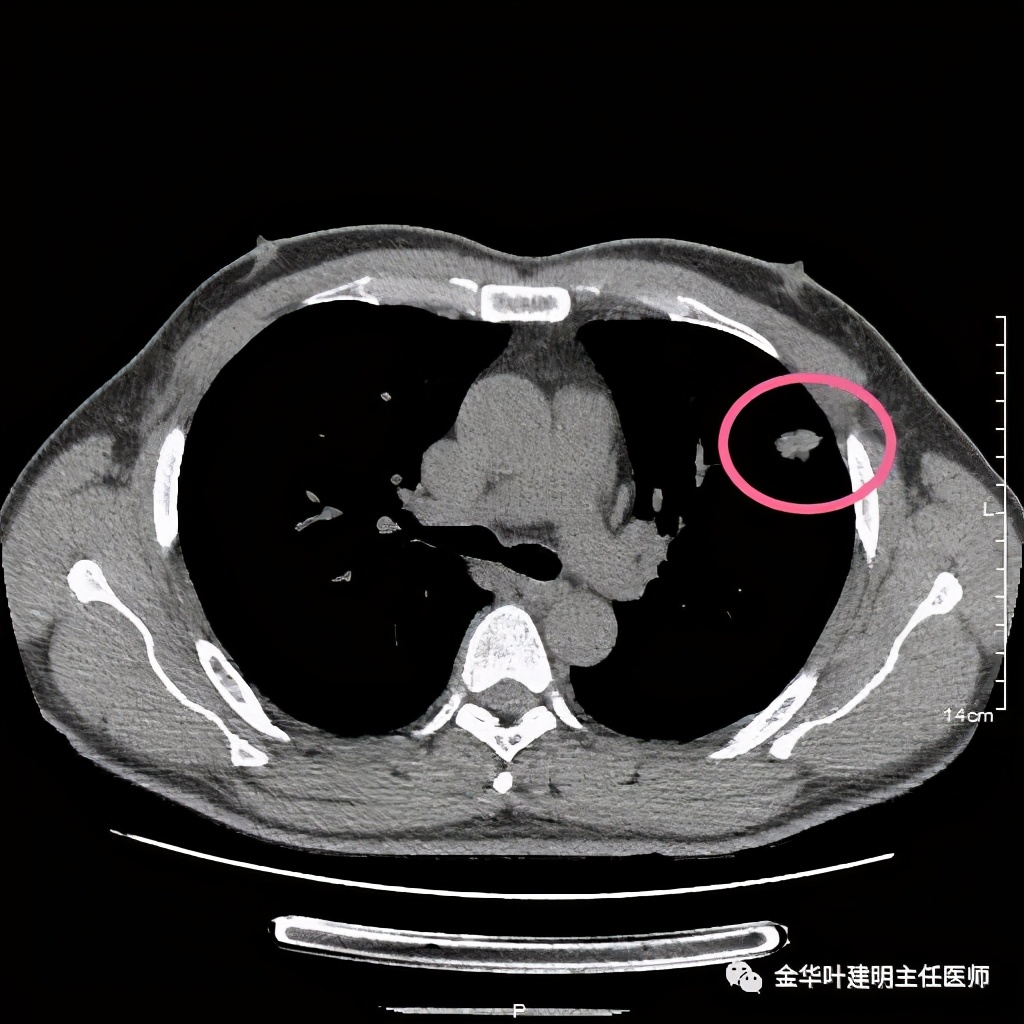

上图示纵隔窗,没有钙化

我们见左上实性病灶,主病灶旁有卫星灶,有血管进入,但也有贴边走行,边缘略显模糊,膨胀感与细毛刺不明显,收缩力也不明显。下面是其靶扫描的片子: